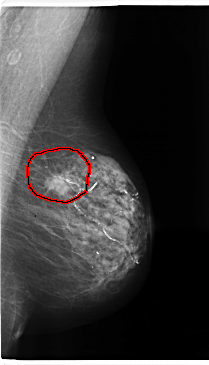

C_0196_1.LEFT_MLO

FILE: C_0196_1.LEFT_MLO.OVERLAY

TOTAL_ABNORMALITIES 1

ABNORMALITY 1

LESION_TYPE MASS SHAPE OVAL MARGINS SPICULATED

ASSESSMENT 5

SUBTLETY 5

PATHOLOGY MALIGNANT

TOTAL_OUTLINES 1

BOUNDARY